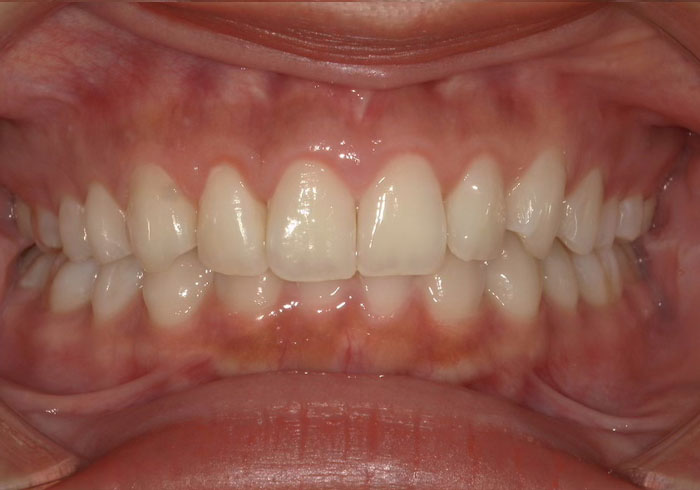

前歯のねじれが気になる

ガミースマイル(笑った時の歯ぐきの露出)も気にされていたので、歯ぐきの処置も併用して治療を行いました。

歯並びが改善されると口周りの筋肉が整い、口角の上がり方も変わってきます。

治療後

主訴 前歯のねじれが気になる。

治療期間 2年半